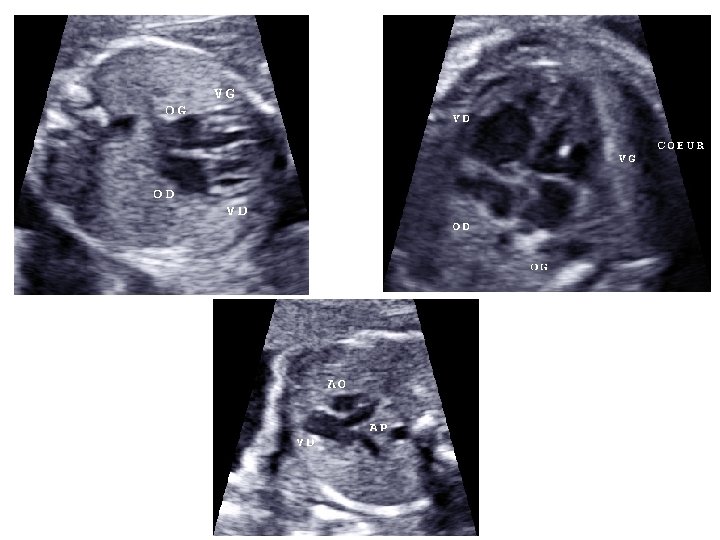

• Étude morphologique approfondie - pôle céphalique : contours de la boite crânienne, volume des ventricules latéraux, structures de la ligne médiane, cervelet (aspect et mesure de sa largeur) - distance inter-orbitaire - coupe nez-lèvre - profil : menton aligné avec le front, mesure des OPN

- thorax : cœur (position, 4 cavités équilibrées, septum inter ventriculaire, croisement Ao/AP), poumons - abdomen : paroi intègre, estomac (position, volume), vésicule biliaire, intestin grêle - arbre urinaire : vessie (position, volume), 2 reins - sexe - rachis avec son revêtement cutané - membres : 4 x 3 segments, 5 doigts aux 2 mains, mouvements d’ouverture des mains, mesure du pied